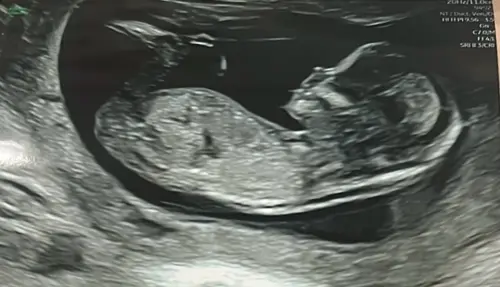

Jongetje of een meisje?

Wat denken jullie? Zou het echt niet weten haha. 13+2 hier.

Niet te zien

Ik zie geen NUB helaas..